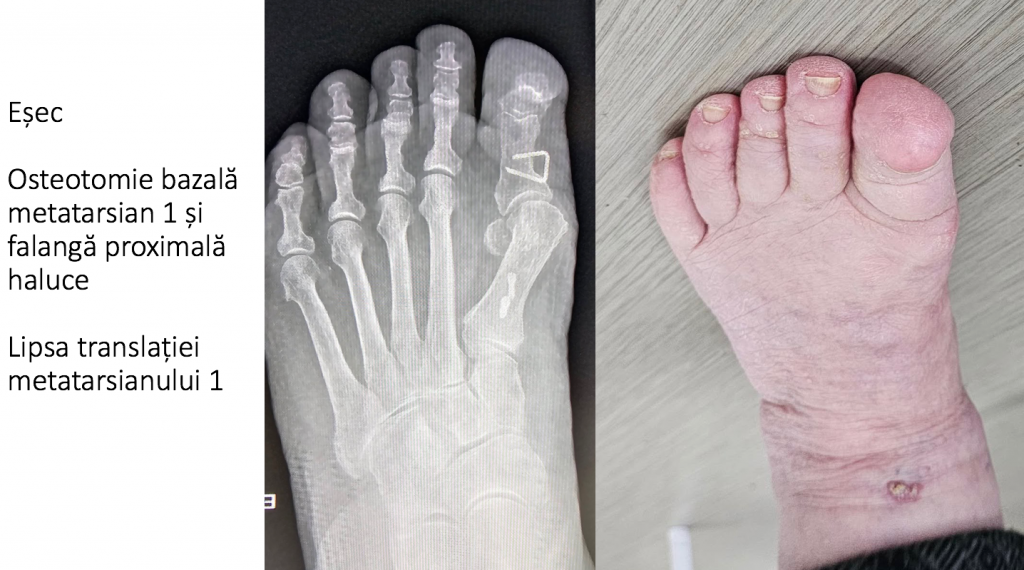

2. HIPO-CORECTIA

- exista o incercare de corectie, soldata cu esec;

- primul metatarsian ramane proeminent dupa incercarea de corectie, iar halucele ramane deplasat catre lateral, in pozitie de valgus;

- poate fi urmarea unei tehnici chirurgicale moderne, dar aplicata necorespunzator (scarf, chevron etc);

- utilizarea unor materiale de osteosinteza inadecvate (brose, sarme, scoabe);

- artrodeza tip Lapidus (desfiintarea prin blocare a articulatiei cuneo-metatarsiene 1) si osteotomiile bazei metatarsianului 1, extrem de raspandite in spatiul anglo-saxon, sunt urmate de complicatii frecvente:

- sunt proceduri intrinsec instabile, datorita bratului lung de parghie ce actioneaza asupra montajului de osteosinteza, pe care-l degradeaza;

- reglarea pozitiei primului metatarsian este dificila si aleatorie in toate cele 3 planuri ale spatiului;

- translatia insuficienta a metatarsianului 1 (dupa osteotomie) este cauza cea mai frecventa a hipo-corectiei;